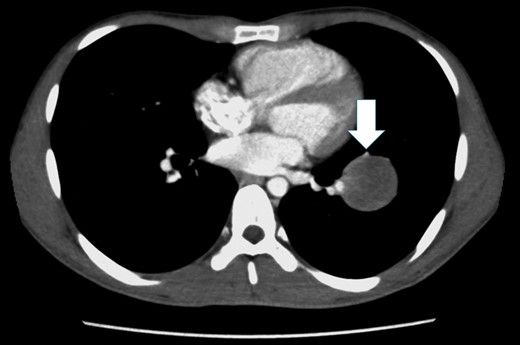

A 26-year-old man underwent arterial switch surgery for transposition of the great arteries in infancy. During a routine evaluation, a nodule was detected in the lower lobe of the left lung on chest computed tomography (CT). At the follow-up examination, the size of the tumor had increased 5 mm each year and he was referred for surgical treatment. Chest CT showed a 40-mm tumor with a smooth margin and a heterogenous inner structure in the left S8 pulmonary segment, close to the interlobar pulmonary artery (PA; Fig. 1). Tumor markers, such as carcinoembryonic antigen, cytokeratine 19 fragment and carbohydrate antigen 19-9, were within the normal range. Positron emission tomography (PET) showed abnormal F-18 fludeoxyglucose (FDG) uptake in the tumor shadow, and the maximum standardized uptake value was 4.66. There was no abnormal FDG uptake in the hilar or mediastinal lymph nodes. We planned to select the operative procedure using intraoperative frozen section examination, because it was difficult to diagnose whether the tumor was benign or malignant.

Chest CT shows a tumor with a smooth margin in the left S8 pulmonary segment, close to the interlobar PA, and the lingular segmental artery is compressed by the tumor (white arrow).